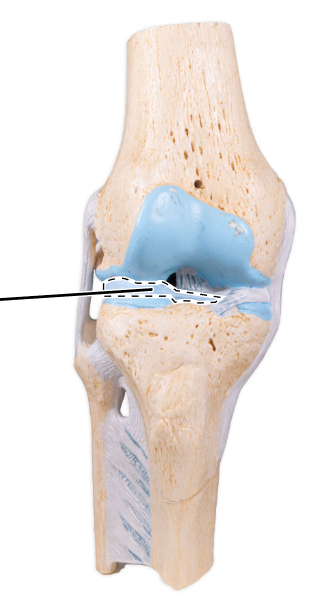

What ligament is shown here?

Posterior cruciate ligament.

What ligament is shown here?

Posterior cruciate ligament.

What does the posterior cruciate ligament prevent?

The posterior cruciate prevents forward sliding of the femur or backward displacement of the tibia.